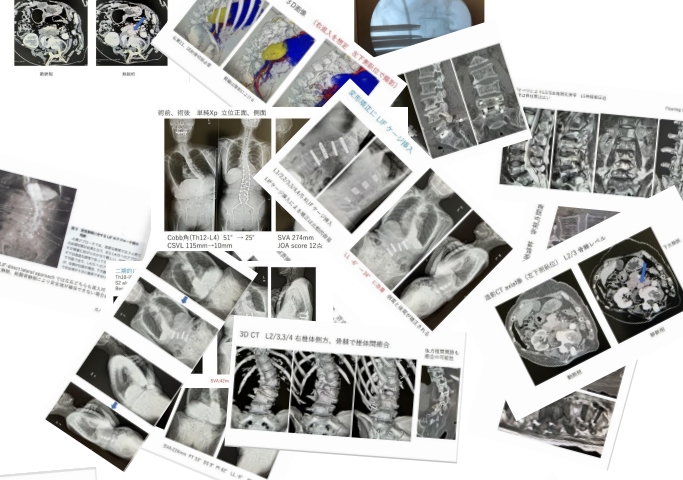

前田先生の自験例の症例、症例の画像を紹介して頂きました。

スライドは124枚、

そのうち、症例紹介、Xp、3D CT、造影CTの画像が、

80枚以上でした。

特に、手術方法等について詳しく説明して頂きました。

スライドも紹介しておきます。